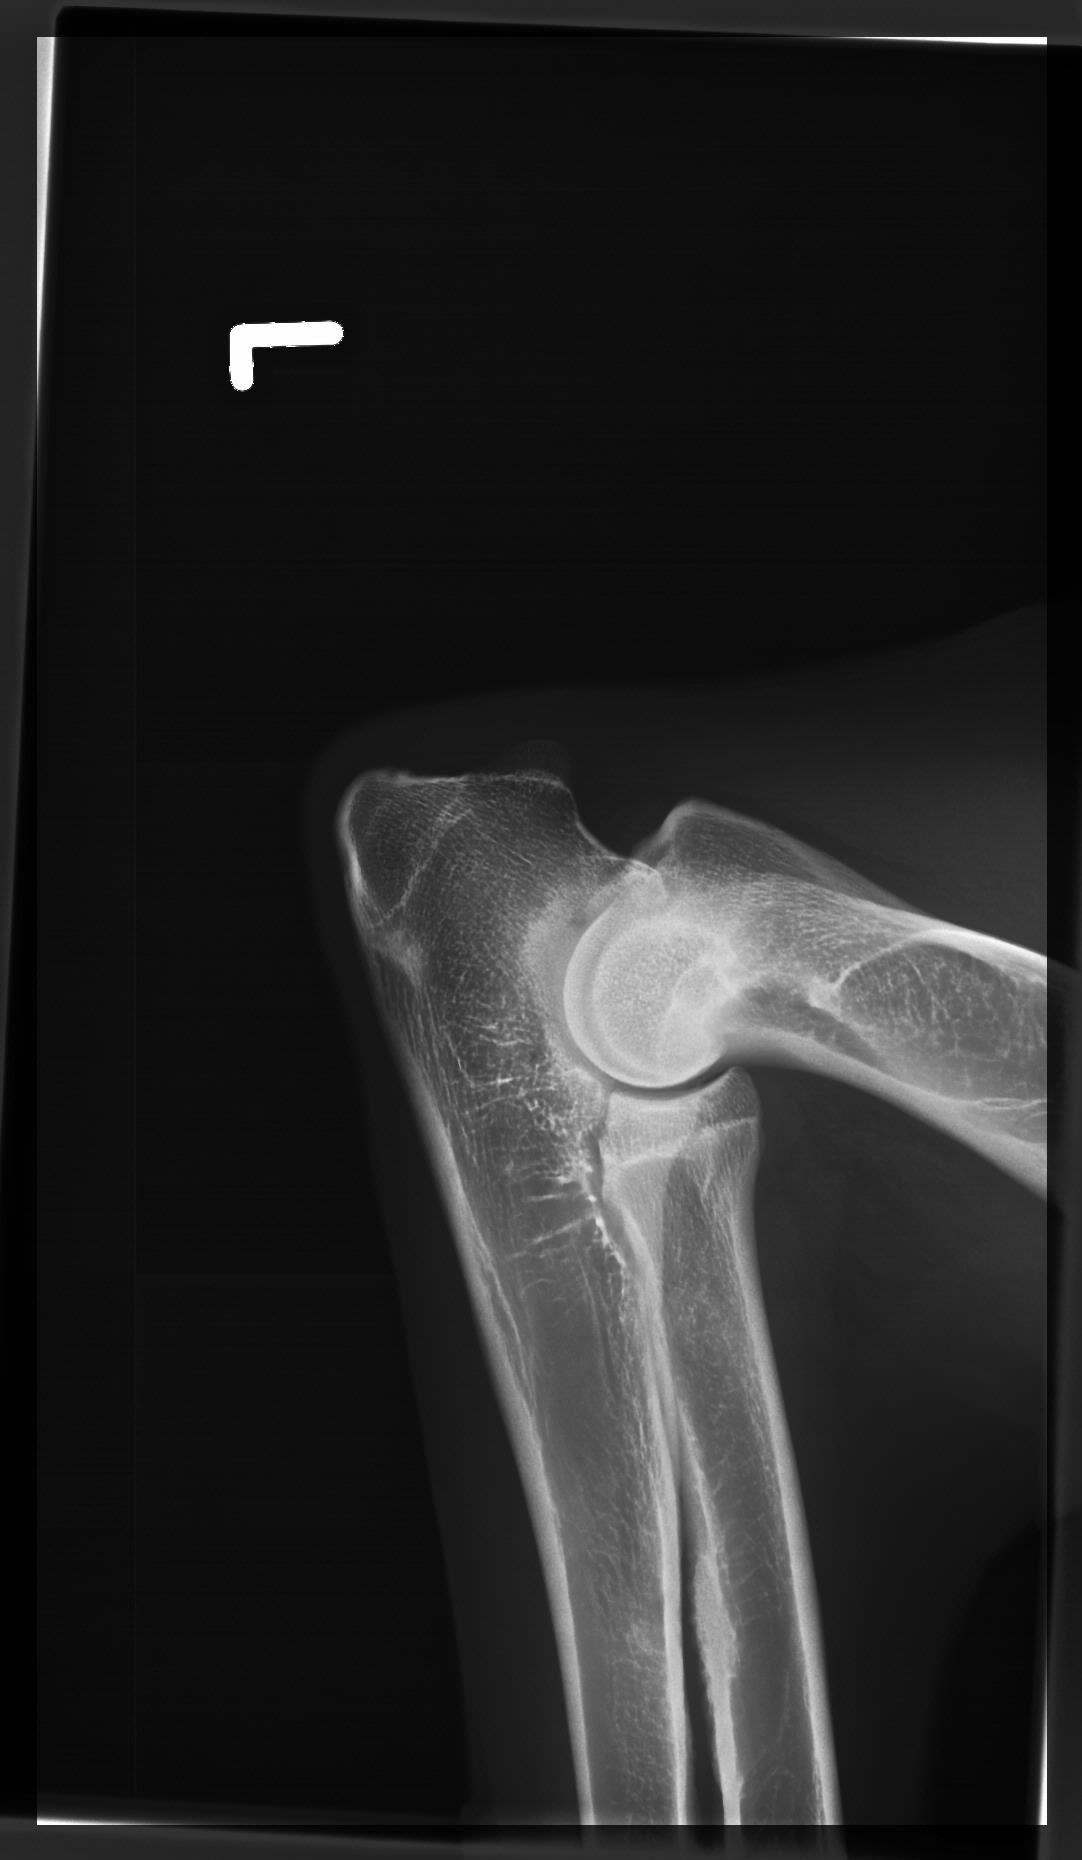

Wir arbeiten mit einer der modernsten digitalen Röntgenanlagen. Diese hochmoderne DR-Flat panel Anlage hat eine der höchsten Auflösungen am Markt und ermöglicht feinste Knochen- und Weichteilstrukturen darzustellen. Diese Eigenschaft ist extrem wertvoll bei der Diagnose von Gelenkserkrankungen wie z.B. einer Ellbogengelenksdysplasie.